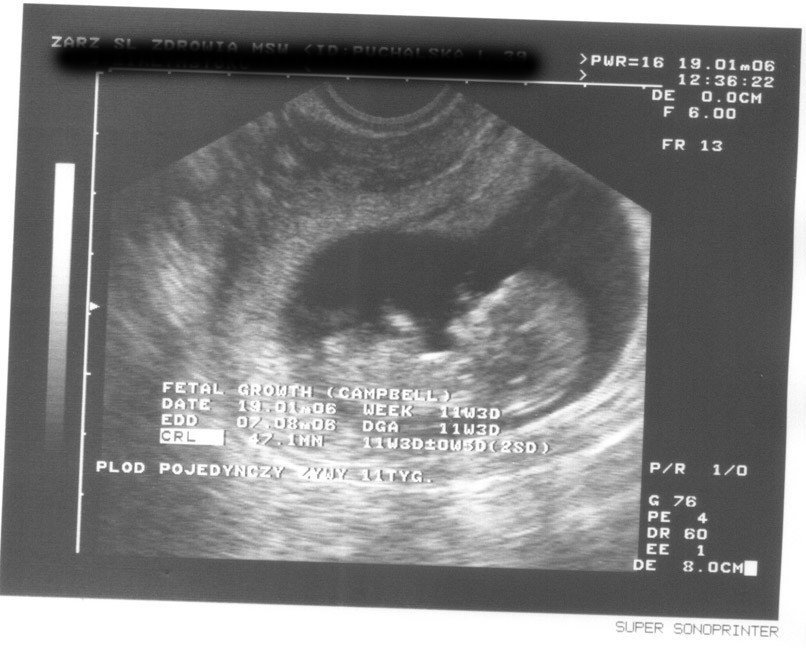

"Ultrasonograficzne potwierdzenie obecności płodu jest możliwe już w 5-6 tygodniu ciąży."